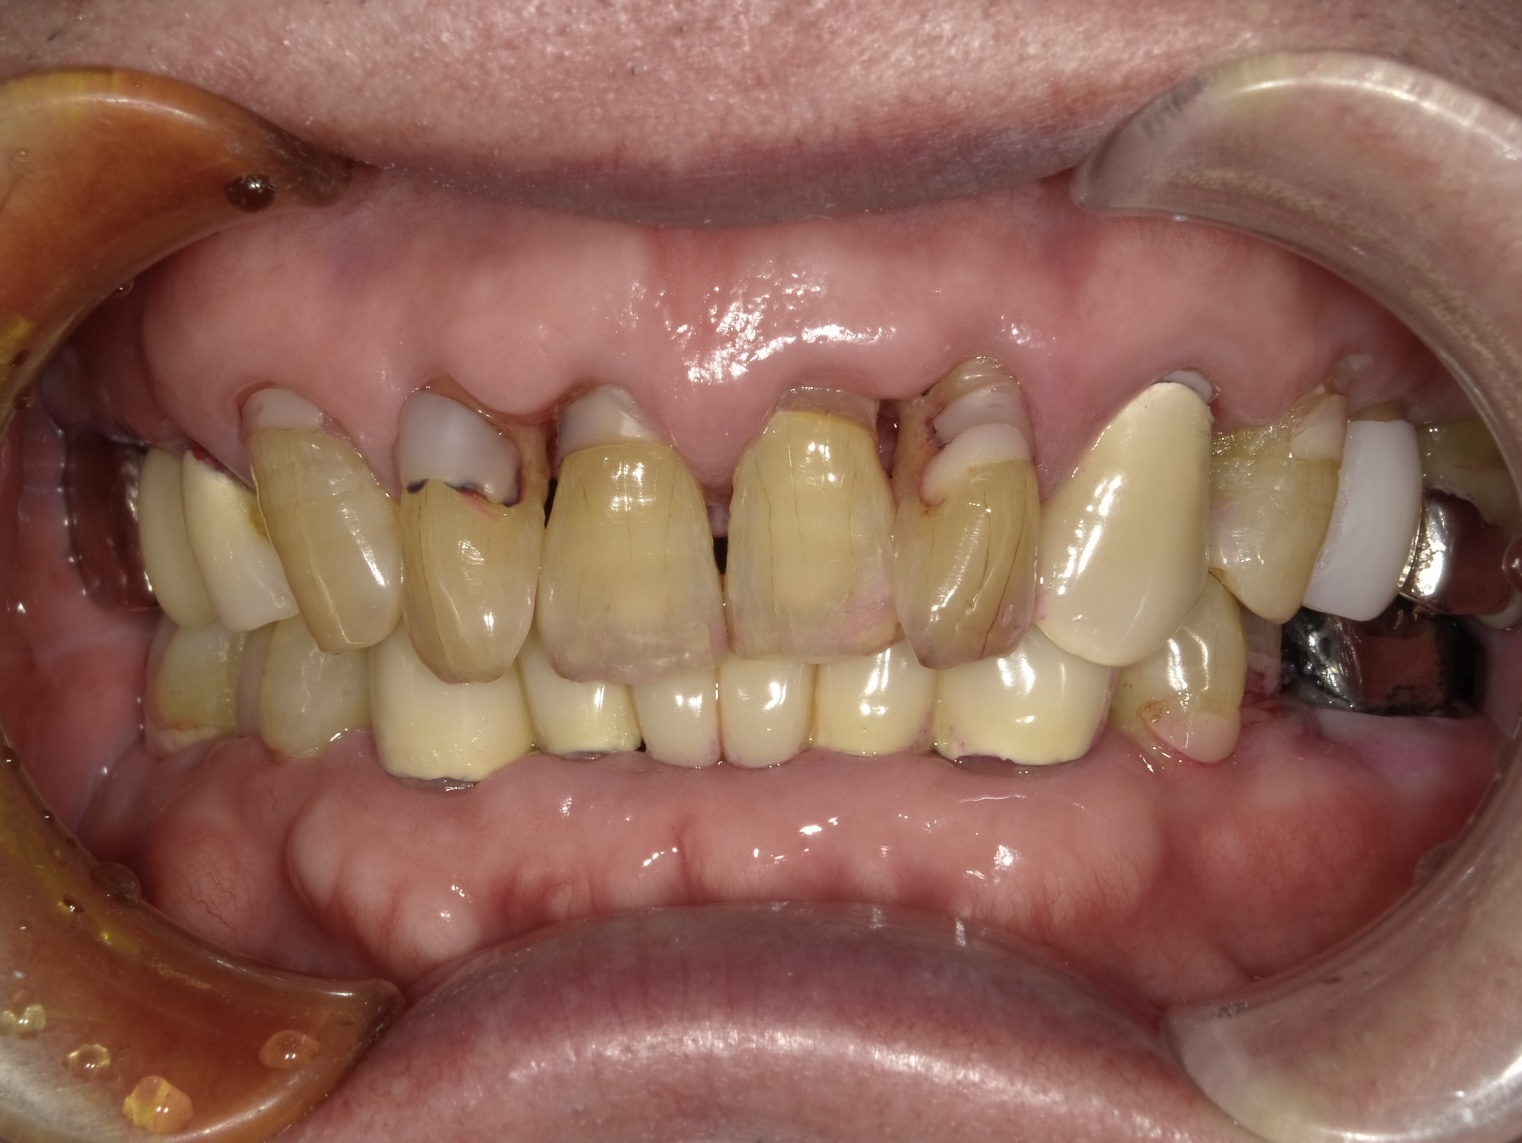

診枚方市藤阪南町にある「藤阪てらしま歯科」は、むし歯や歯周病などの一般治療はもちろん、目立たず歯を美しく整えるマウスピース矯正や、0期から始める小児矯正「マイオブレイス矯正」などの治療にも力を入れています。患者さま一人ひとりに寄り添い、健康で美しい歯をサポートいたします。

虫歯治療decay

歯周病perio

咬合治療occlusion